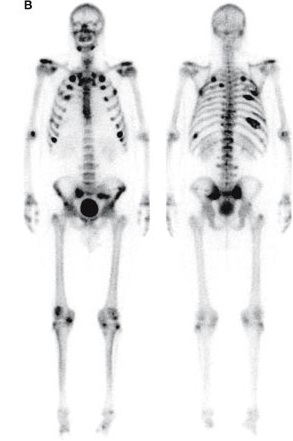

Depistarea prezenţei metastazelor osoase, mai ales în cancerele pulmonare, mamare şi prostată, reprezintă cea mai frecventă indicaţie a scintigrafiei osoase, deoarece nu există altă metodă de detecţie mai rapidă şi ieftină. Scintigrafia este uşor de realizat, sensibilă şi fără contraindicaţii şi deosebit de utilă pentru stadializarea afecţiunii, mai ales ţinând cont că circa 30% dintre pacienţi au deja metastaze osoase în momentul diagnosticului. Scintigrafic, metastazele osoase vor apărea ca multiple focare, hipercaptante diseminate la nivelul întregului schelet. Multe dintre leziuni sunt nevizualizabile pe imaginile radiografice, cu o simptomatologie minimă, scintigrafia permiţând astfel detectarea acestora cu mult timp înainte de a fi vizualizate radiografic.